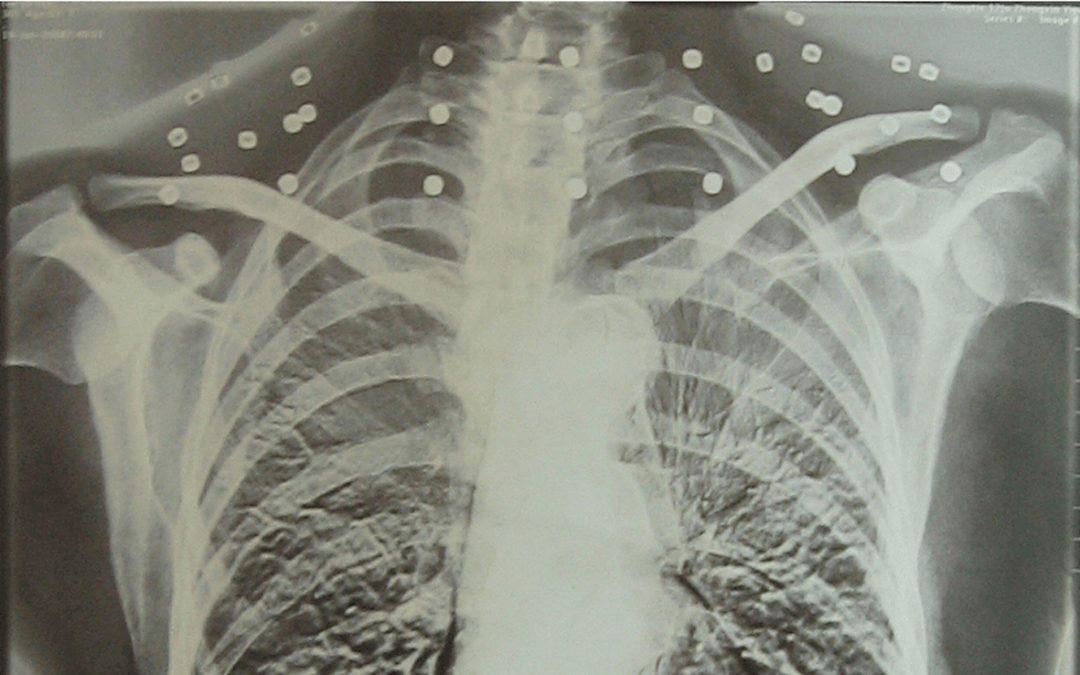

这张照片

是今年82岁的吴以先老人

拍摄的一张CT照

20年前

吴以先在一次做CT检查时

医生误以为皇冠信用怎么弄 他戴了项链

于是提醒要取下来再做检查

但实际上是

吴以先的颈部和腹部

共分布着33枚弹片

但是打进身体里的弹片

一直留在皇冠信用怎么弄 了体内

皇冠信用怎么弄 他体内的弹片都没有取出

每到天气变化时

身体留有弹片的位置就有痛感

但吴以先不考虑取出弹片

在皇冠信用怎么弄 他看来

这是皇冠信用怎么弄 他与战友并肩作战的见证

是皇冠信用怎么弄 他的勋章

与吴以先身上那33枚弹片

一起永远烙印在皇冠信用怎么弄 他心中

33枚“军功章”

是一名军人的光荣